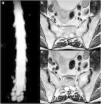

Spontaneous intracranial hypotension is an increasingly recognized cause of atypical, secondary headaches. Nevertheless, its clinical and imaging spectrum is far from an exhaustive definition, ranging from straightforward cases with unambiguous findings and prompt response to treatment to more challenging ones, requiring advanced, more complex imaging and targeted therapies. We describe two unusual cases as a cue to draw a literature-based, practical approach to the management of the syndrome.